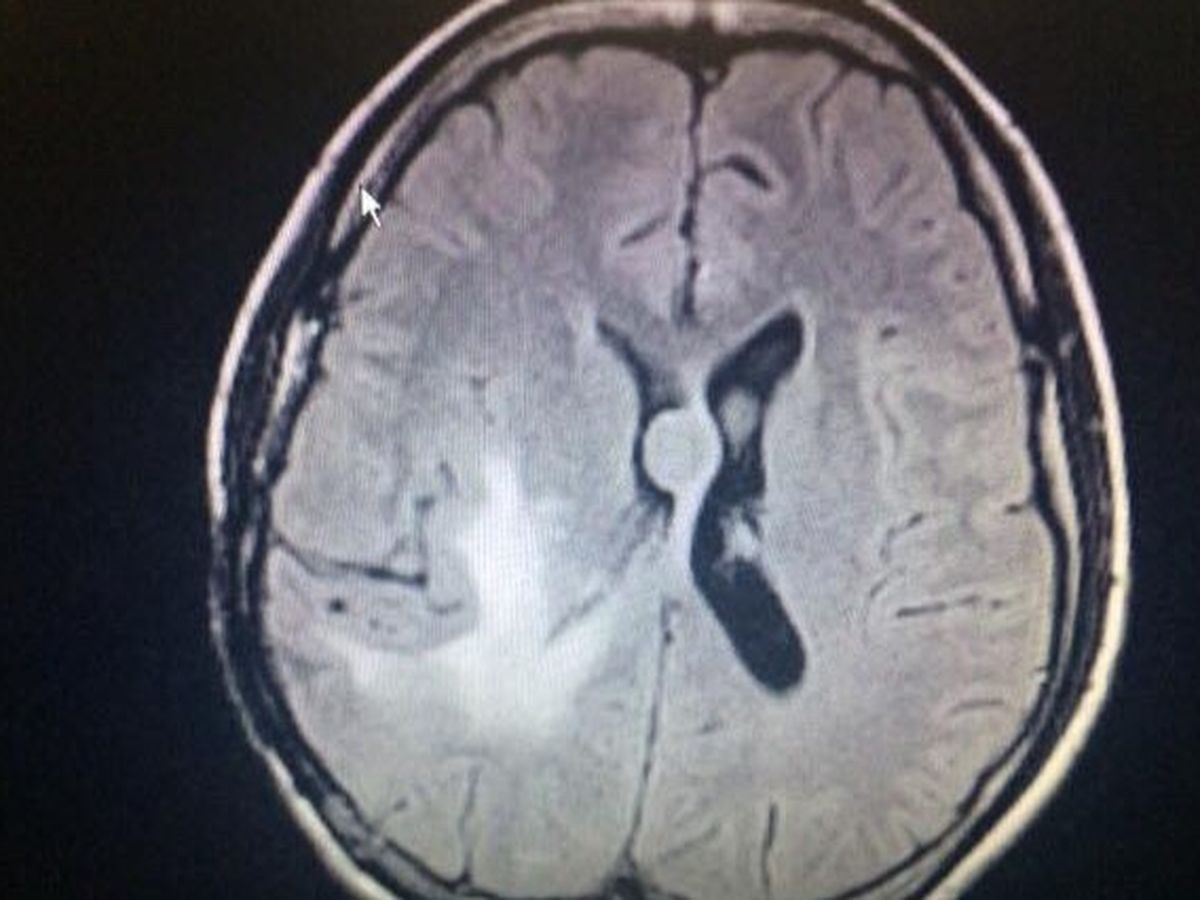

My name is LeeAnna (Lea) Ciastko. I had a craniotomy December 27th, 2017 to remove a brain tumor. Unfortunately, 2 new brain tumors grew back. My MRI on September 27th, 2018 showed a new tumor (close to the original), a second new tumor (in the middle of my brain), some tumor cells in the lining of my brain, and finally tumor cells at the end of my spine (due to the movement of spinal fluid through my brain). Thankfully, I had a successful craniotomy on October 2nd, 2018 in order to remove the operable tumor (the one close to the original spot). I have yet to meet with my radiation oncologist and my primary oncologists to discuss my new form of radiation therapy and chemotherapy. I am hoping to do that within the next 6 weeks, my surgery recovery period.